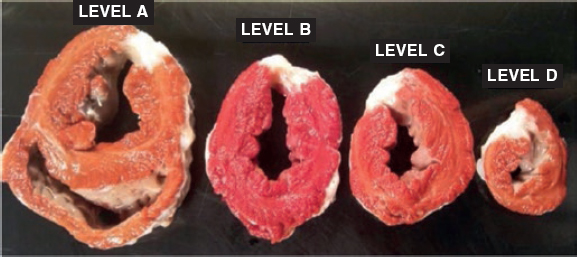

A complete, organized, and systematic necropsy of each animal corpse was conducted to identify and diagnose any possible conditions associated with the procedure. The samples obtained were fixed in formaldehyde at 10% for histopathological study. In the macroscopic study of the heart, its weight was recorded and its cavities, walls, papillary muscles, mitral chordae tendinae, annulus, and valve leaflets analyzed. All the possible anomalies seen in these structures were documented photographically. Afterwards, the leaflets were extracted from their insertion location and up to their free borders including their chordae tendinae and they were fixed in formaldehyde at 10% and included in paraffin for histopathological study. Three µm thick serial sections were stained with the usual hematoxylin and eosin technique; the Van Gieson elastin stain protocol was used to study elastic and collagen fibers; the Masson trichrome stain protocol was used to differentiate muscular from collagen fibers; finally, the alcian-blue PAS staining protocol was used for the detection of mucopolysaccharides. The histopathological changes identified were semi-quantitatively assessed by establishing the different degrees of damage.

After collecting the leaflets to characterize the infarction, another 4 cross-sectional cuts were performed from the vertex of the heart towards its base. They were weighted and stained with triphenyltetrazolium chloride histochemical staining to enhance the viable area (red color) of the necrotic region (white color). For that purposes, the levels established were submerged in a solution of triphenyltetrazolium chloride (Sigma-Aldrich) at 1% in a phosphate buffered saline solution (pH 7.4) for 5 to 10 minutes at 37 °C, and then they were submerged in formaldehyde at 10%. The sections were photographed, and the areas measured using the Image J system. Samples of the infarction region, limit, and non-infarcted region were collected from every level, submerged in paraffin, and stained using the hematoxylin and eosin technique and the Masson trichrome stain protocol to characterize ischemic damage.

The macroscopic examination revealed an infarction region in the lateral side from apical to basal level. The use of triphenyltetrazolium chloride stain confirmed the occurrence of a transparietal infarction (figure 2) whose size is shown on table 1 of the supplementary data together with the weight of each level.

Figure 2. Animal #1. Presence of transparietal infarction areas from basal (A) to apical level (D). Triphenyltetrazolium chloride stain.